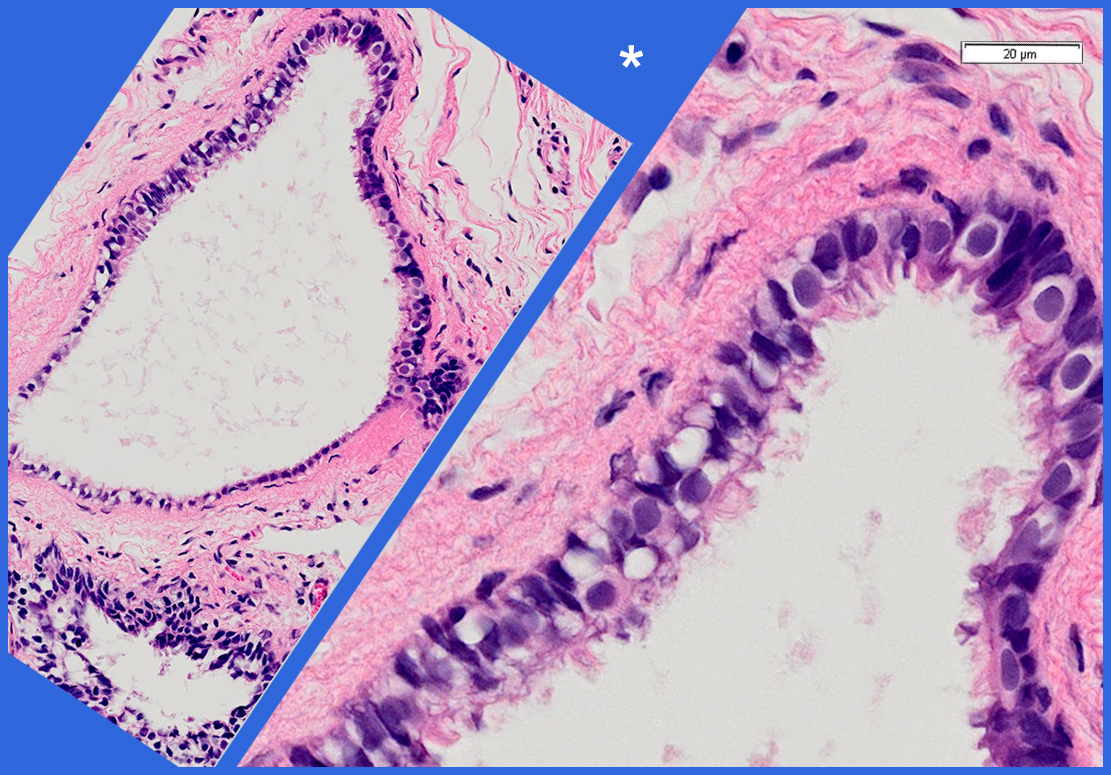

Bei Frauen bestehen kleine gestielte, mit Flüssigkeit gefüllte Bläschen am Fimbrientrichter des Eileiters als zystische Ausweitung des Wolffschen Ganges von 2 bis 10 mm Größe. Meist findet man solche Hydatiden als Zufallsbefunde bei Bauchspiegelungen. Eine operative Entfernung ist sinnvoll, wenn sie größer sind und die Gefahr einer Stieldrehung besteht.